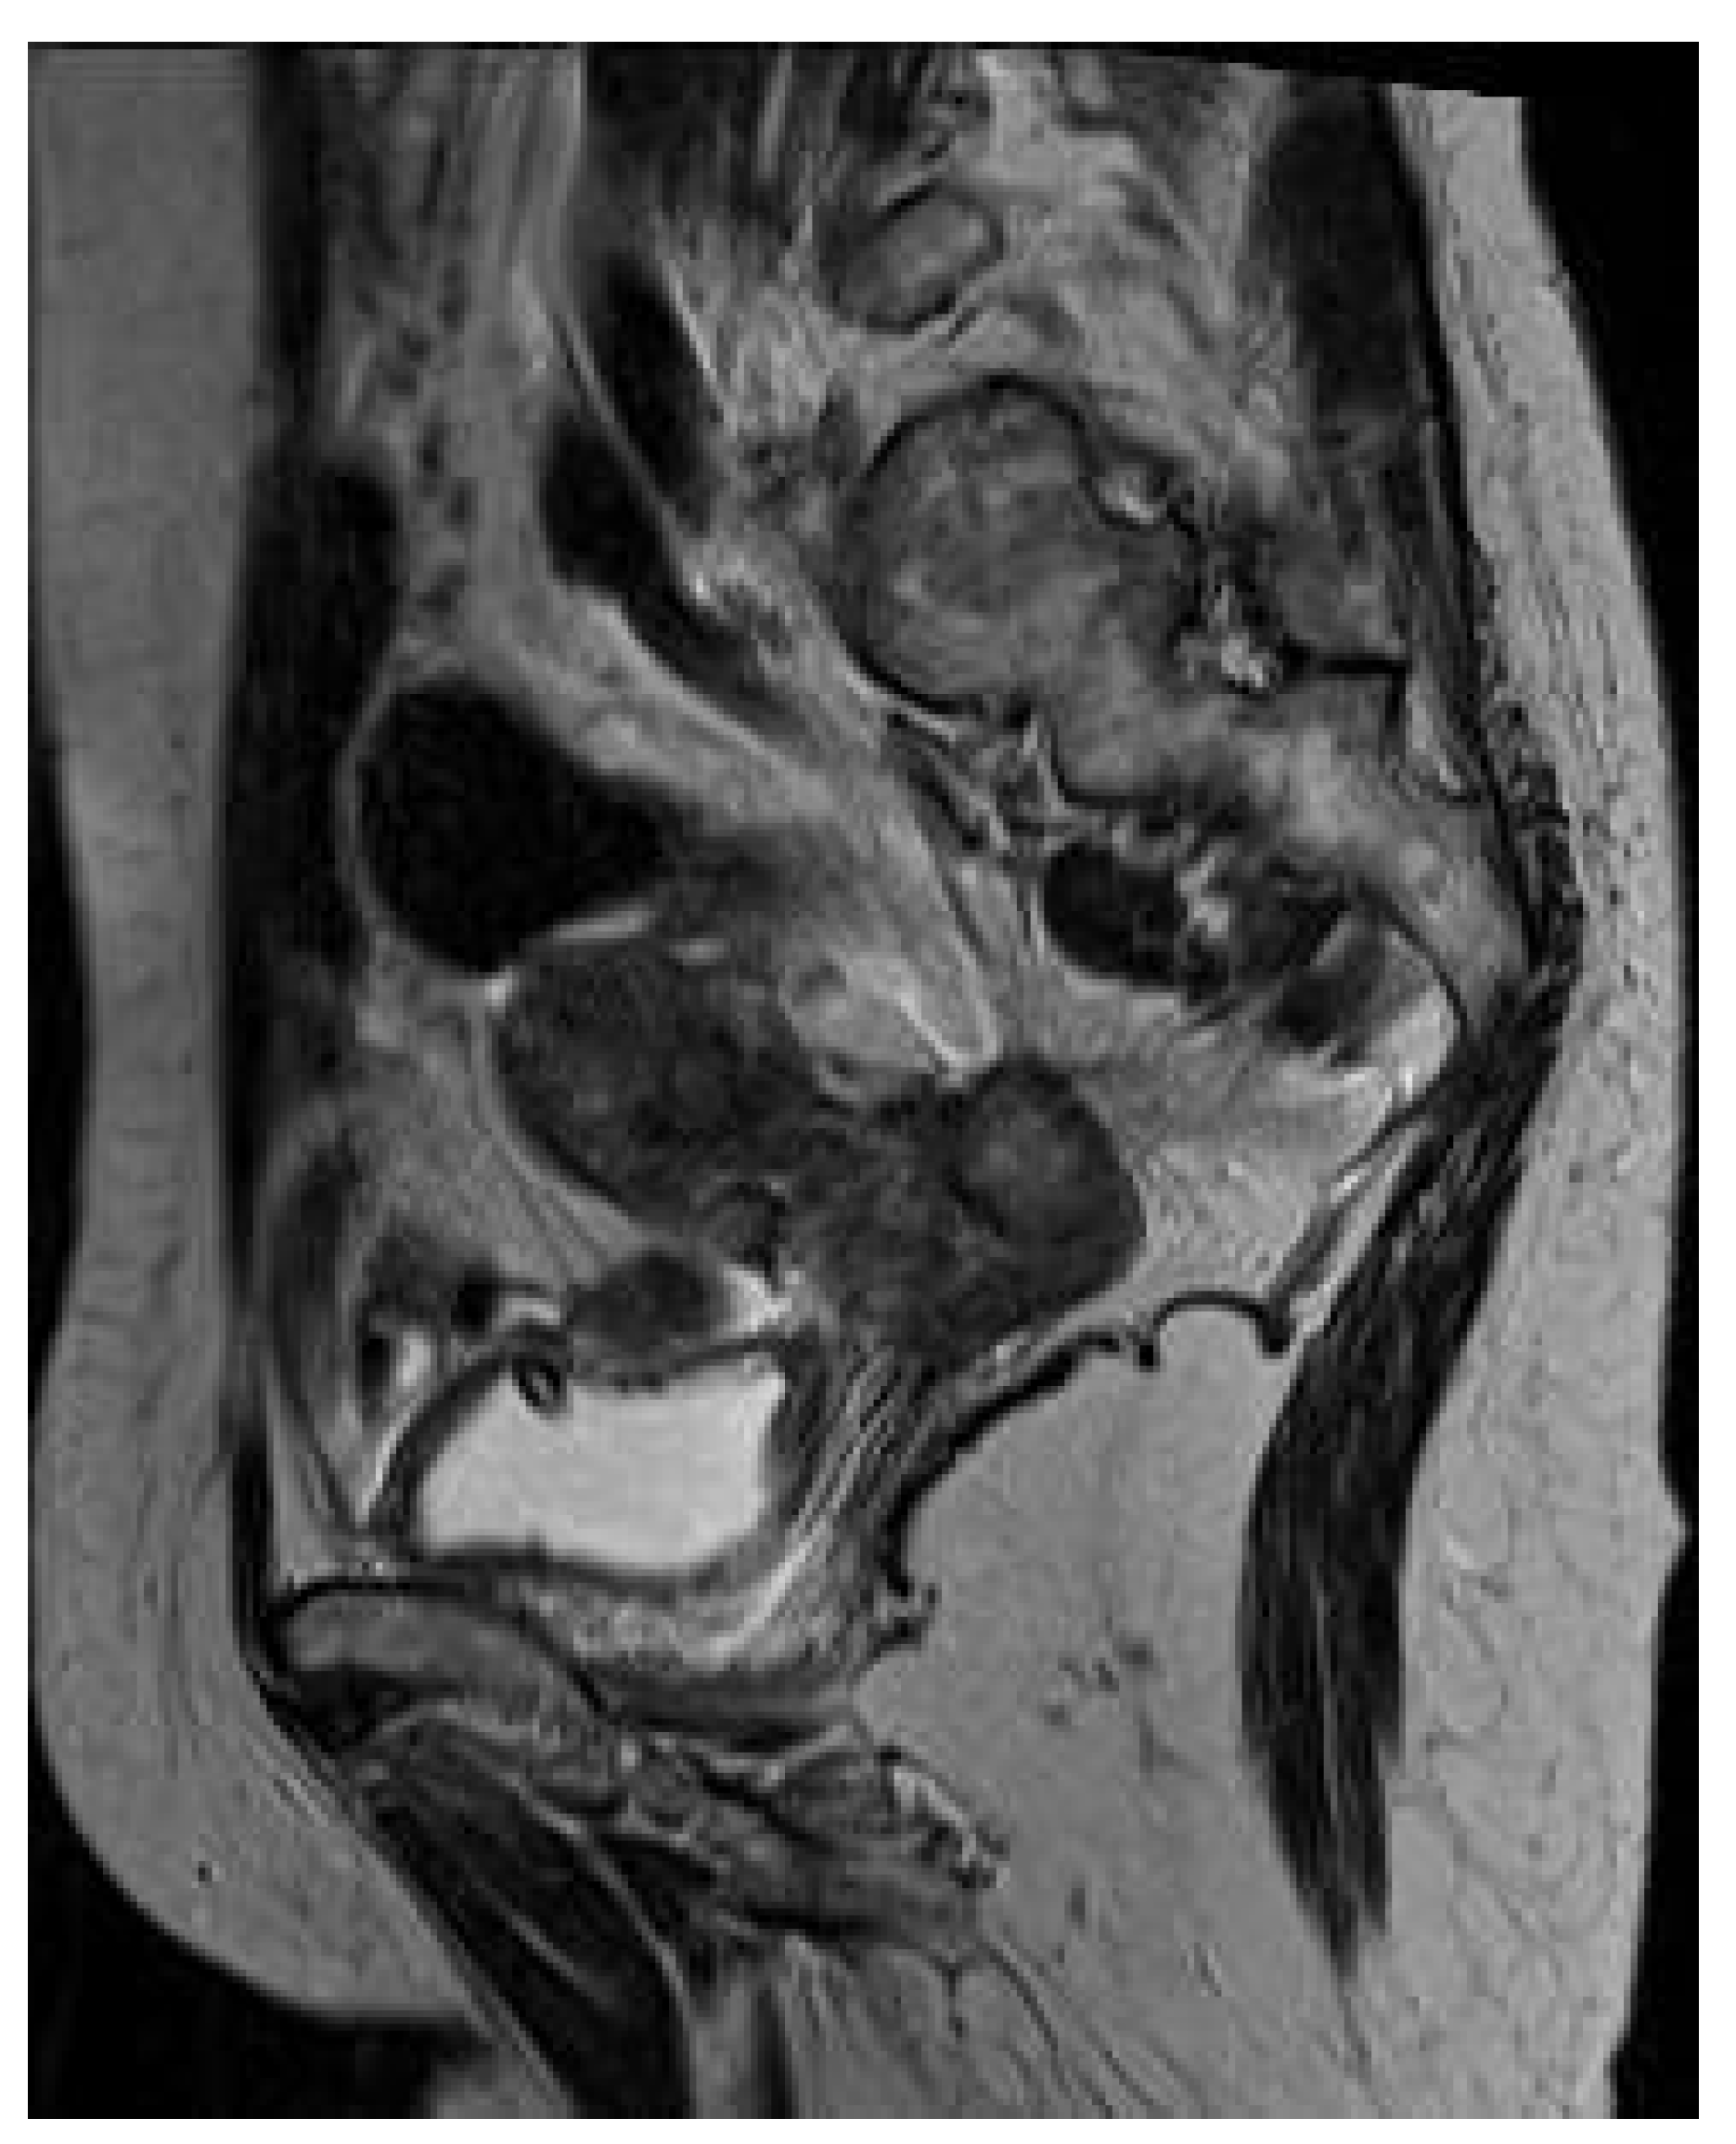

Krukenberg Tumor in Association with Ureteral Stenosis Due to Peritoneal Carcinomatosis from Pulmonary Adenocarcinoma: A Case Report

2. Case Report